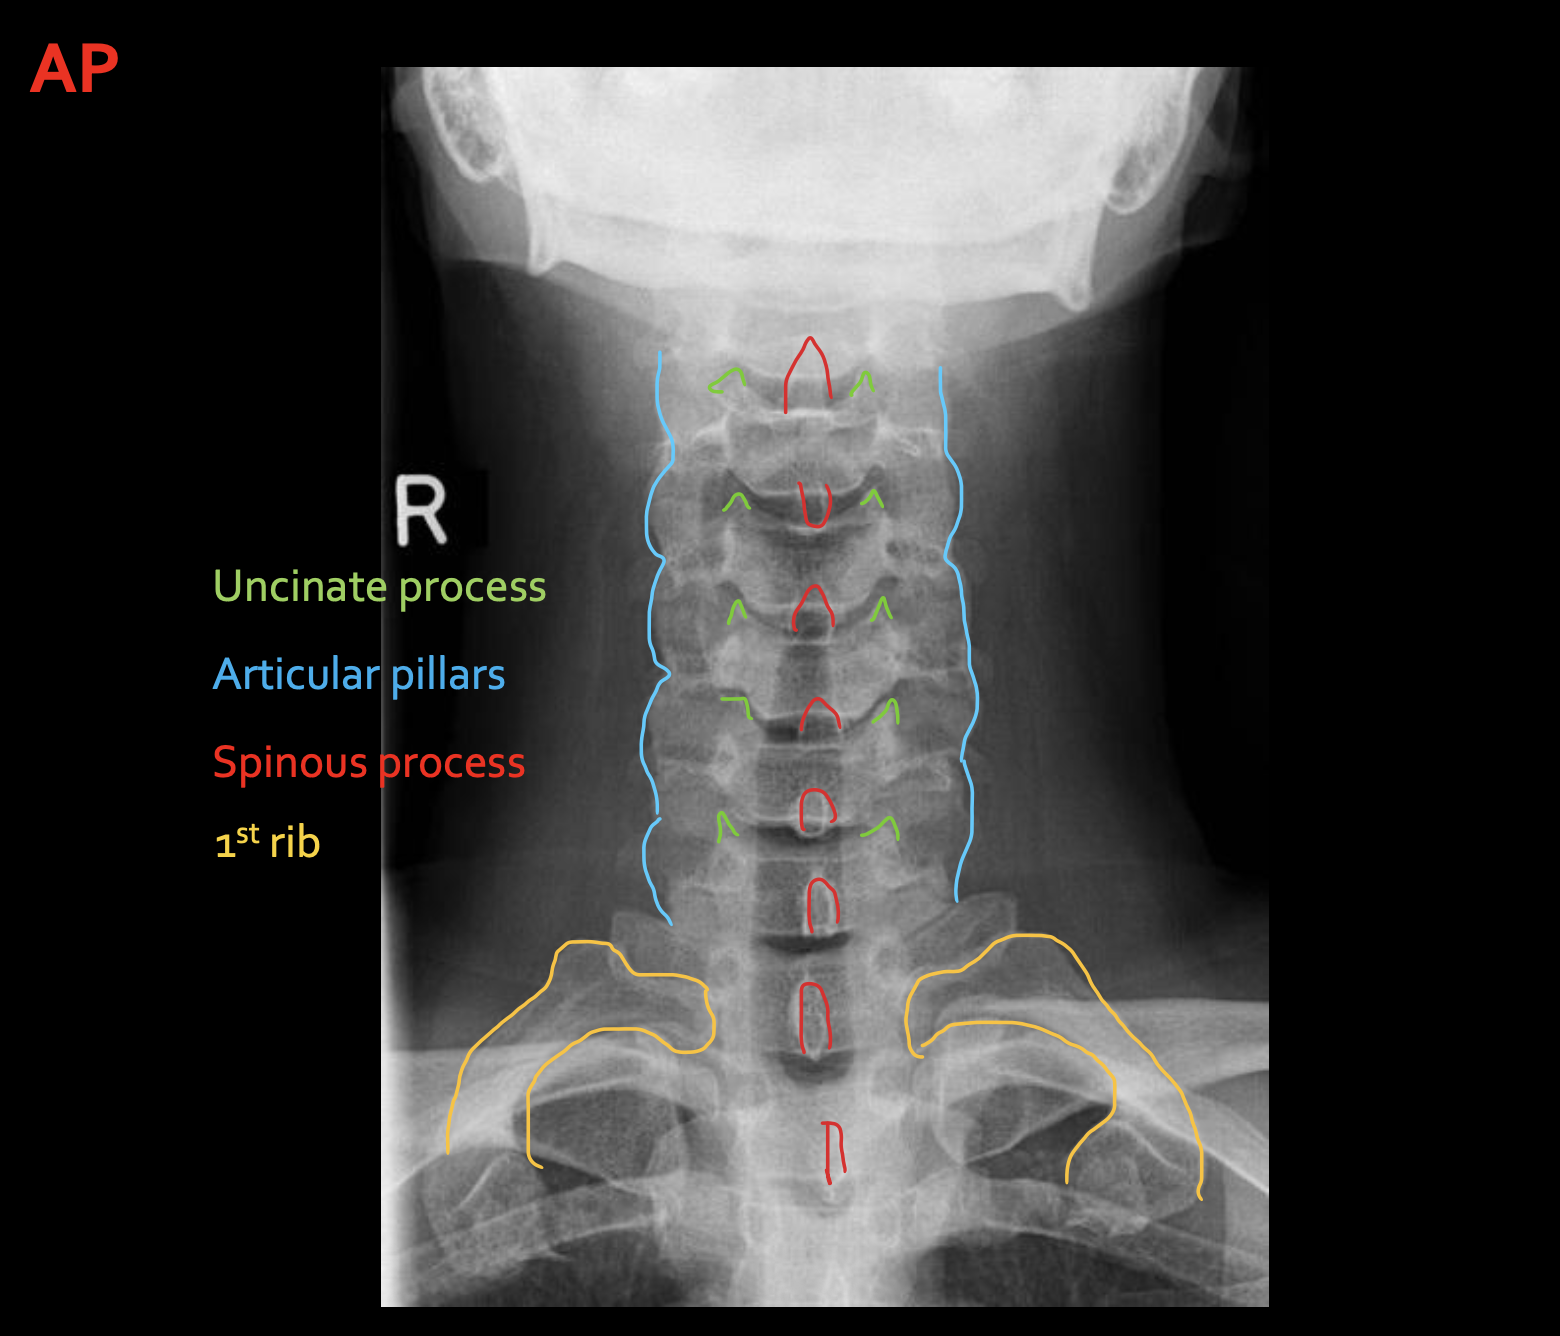

钩突

Uncinate process

关节柱 / 侧块

Articular pillars

棘突

Spinous process

T1

1ST Rib